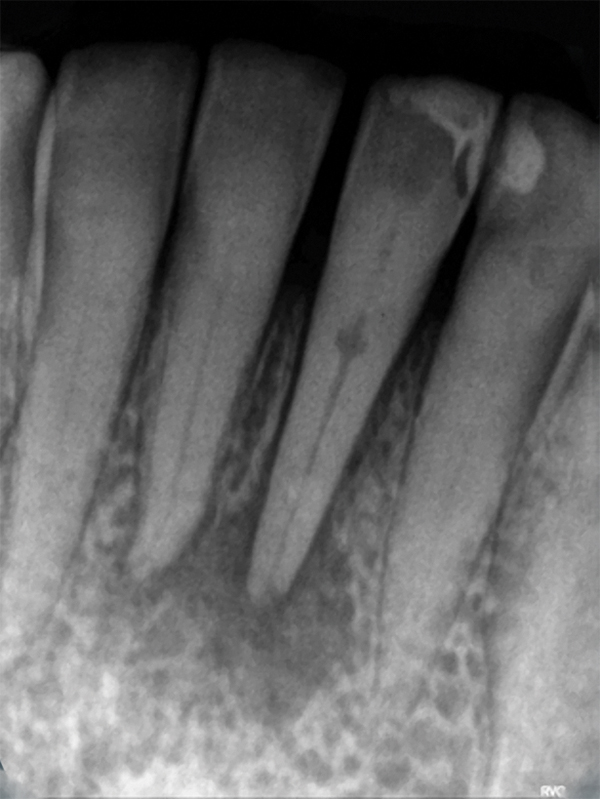

Invasive Cervical Root Resorption Inside Dentistry